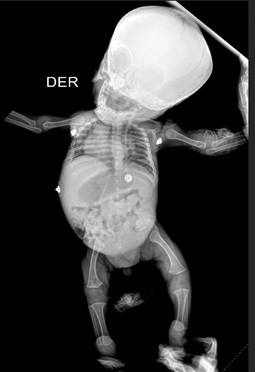

Acondroplasia congénita a partir de una mirada multidimensional. Reporte de caso

Laura Beatriz Rojas Londoño, Alejandra Villa Bustamante